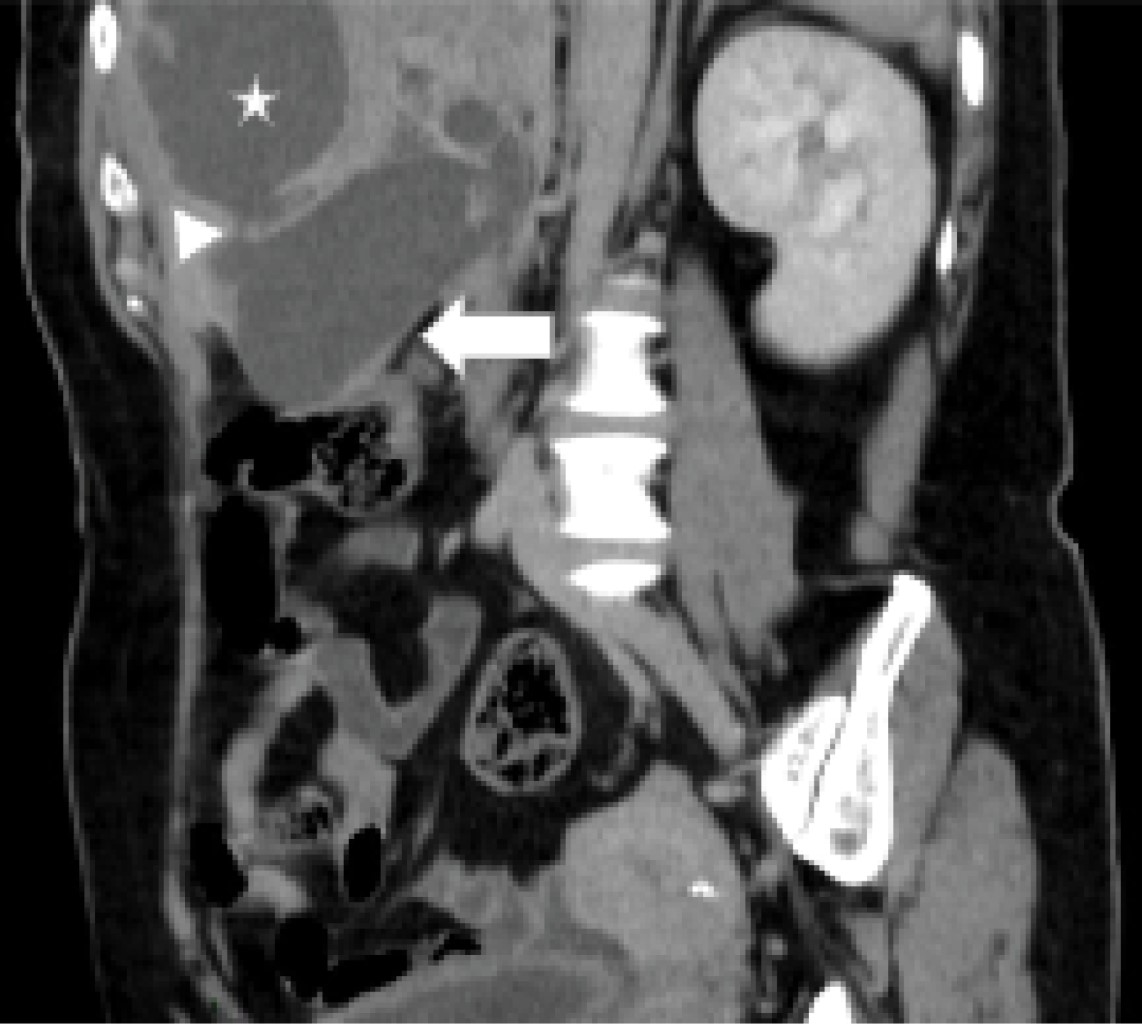

A 55-year-old female patient came to the emergency department with a picture of a month of evolution characterized by abdominal pain located in the epigastrium and right hypochondrium, radiating to the interscapular region, which was increasing, so she decided to go to the doctor who started homeopathic treatment; however, she did not improve, so she went to the emergency department of our hospital unit where the following vital signs were recorded: BP (blood pressure) 114/76 mmHg, HR (heart rate) 124 bpm, RR (respiratory rate) 16/min, and temperature of 36 °C. On questioning, the patient denied the presence of fever, nausea, vomiting, or the presence of bowel movements of decreased consistency. For her approach, general laboratories were requested, highlighting the presence of leukocytosis (12,300 mm3), elevated alkaline phosphatase, and GGT (315 and 268 U/l respectively); a CT scan of the abdomen with intravenous contrast was requested (Figures 1, 2 and 3) which showed the presence of gallbladder with impacted lithos in its interior, and an intrahepatic rupture, in addition to an intrahepatic abscess in segments IV and V (Figure 2).

Figure 3